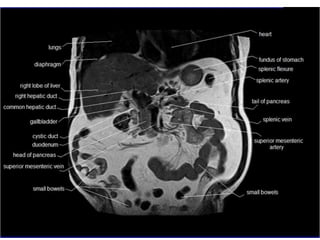

LIVER

Upper margin: level with

xiphisternal joint, 5th intercostal

space 7-8cm from midline; on L,

5th rib on R.

R border: ribs 7-11 in mid-axillary

line.

Lower border partly lies along

right costal margin, crosses in

upper abdominal wall, hands

breadth below xiphisternum

PANCREAS

The surface projection of

the head of the pancreas

lies within the duodenal

curve.

The neck lies in the

transpyloric plane, behind

the pylorus in the midline.

The body passes obliquely

up and to the left for

approximately 10 cm, its

left part lying a little above

the transpyloric plane.

The tail lies a little above

and to the left of the

intersection of the

transpyloric and left lateral

planes.

ABDOMINAL AORTA